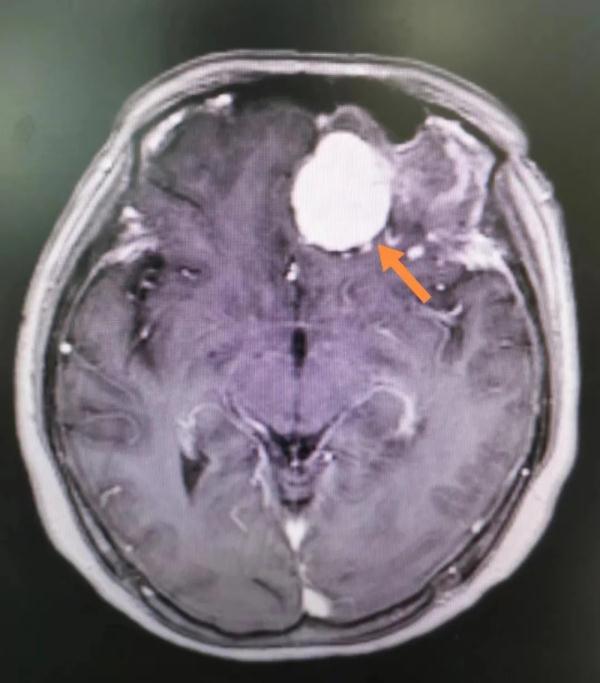

△術前核磁共振可以清晰地看到患者顱內(nèi)腫瘤(箭頭所示)

入院完善頭部核磁共振檢查發(fā)現(xiàn),患者前顱底深處有一顆肉丸大小的腫瘤,考慮為良性的腦膜瘤。通過詳細的術前討論后,于8月19日在全麻下為其施行開顱腫瘤切除術。